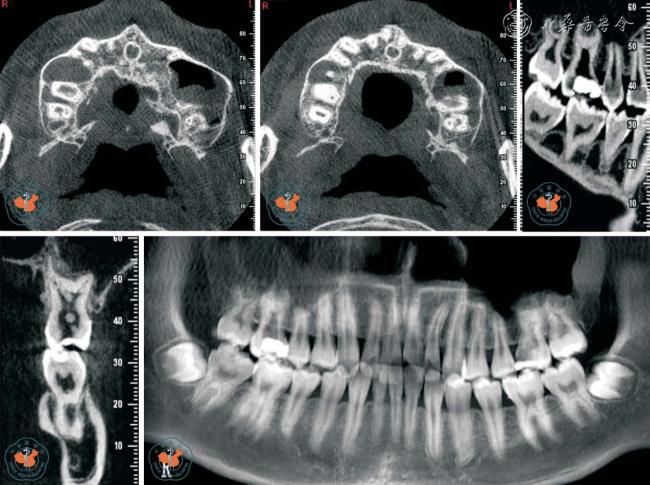

3. 对根管治疗术质量的评价:CBCT 图像可了解牙髓组织的解剖结构,特别是在复杂根管治疗前及术中,可以随时调用近远中向、冠根向、颊舌向的解剖图像,从不同的方向及断层进行切片分析,能够清晰地了解根管的形态,帮助根管治疗,使治疗更彻底,根管治疗后还可以用来监测根管治疗效果,减少了漏诊(图5)。

图5 CBCT 轴位、CPR 及MPR 重建冠、矢状位图像清晰显示上颌第一、二磨牙(牛牙症)

4. 对牙根折根裂诊断的意义:牙根折裂临床上分为纵折、横折及斜折三种类型。 在很多情况下,牙根折(特别是纵折)一般不易在根尖片上清楚显示,只表现为患根周围的牙周膜增宽,或出现J 形牙槽骨吸收,而看不到明显的根折线。 另外由于投照角度可影响X 线片的检出率,加上重叠的解剖关系干扰了读片医生的判断能力,因而早期患者经常存在漏诊。 而CBCT 则可以通过矢状面(近远中向)、冠状面(颊舌向)及水平面(冠根向)清晰的显示出根折线,同时清晰的显示出根折位置及类型,也可以对传统的根尖片疑似根折的病例用三维立体的图像进行直观的分析以明确诊断(图6)。 Hassan 等14研究显示,X 线与CBCT 对牙根纵裂的诊断能力,并评估根充材料对诊断牙根纵折的影响,结果显示CBCT 对诊断牙根纵裂的敏感度及特异度分别为79.4%与92.5%,根尖片发现牙根纵裂的敏感度及特异度分别为37.1%与95%,CBCT 检出牙根纵折的准确度明显高于根尖片。 另外,Hassan 还分析了根管充填材料对于牙根纵折检出的影响。 结果表明根充材料的存在降低了CBCT 的特异度,但未影响其准确率。 而对于根尖片,根充材料的存在既降低了其敏感度,也对其准确率造成了影响。 尽管CBCT 有上述优势, 但应注意致密根充材料和金属桩核在CBCT 图像中造成的高低密度混杂的放射状伪影,会产生与根裂纹相似的影像,应仔细辨别,以防误诊15

图6 CBCT 轴位、VR 及MPR 重建冠、矢状位图像清晰显示根折线